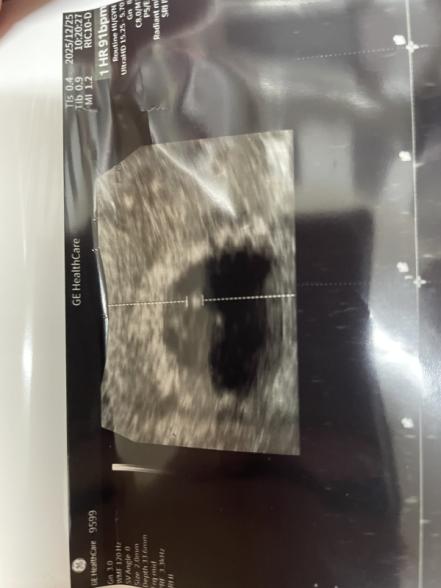

しかし、12/25の7w3dの妊婦健診の際に、何とか心拍を確認することは出来ましたが、胎芽が小さい。とのこと。

ピクピク心臓が動いているのは分かりましたが、胎芽は2ミリ程でした。